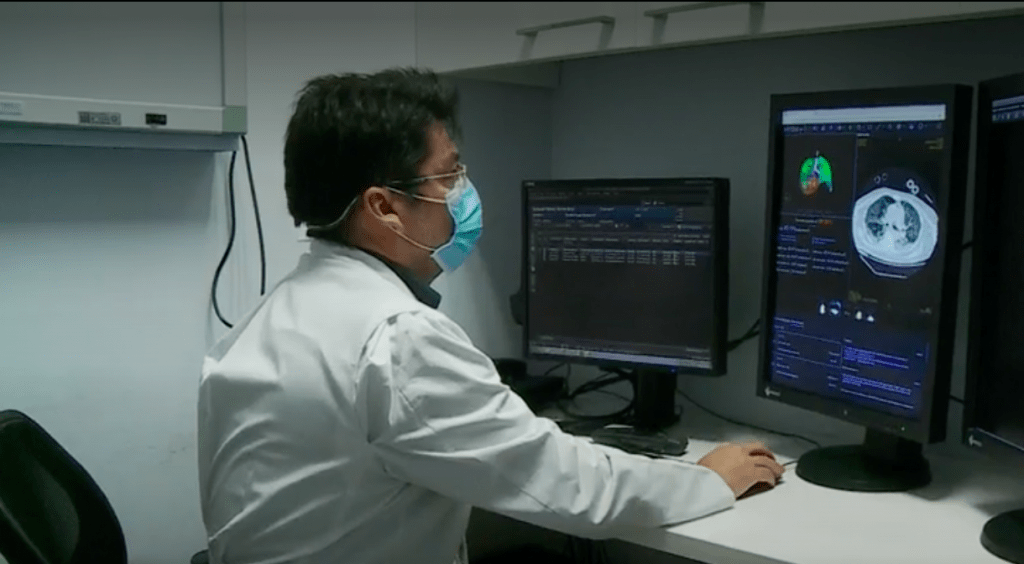

Para hacer frente a esta situación, Huawei donó un innovador sistema de detección, del Covid-19, al Hospital de Urgencias Ex Posta Central. Innovación que utiliza inteligencia artificial para detectar, tempranamente, los casos positivo o descartar los negativos. Para que dicha tecnología funcione de manera correcta, la compañía china cuenta con una alianza con Entel.

El funcionamiento de esta innovación se basa en los datos almacenados en la nube. Para esto, se le realiza un escáner de los pulmones al paciente sospechoso. Estos resultados serán comparados, a través de la inteligencia artificial, con más de 4.000 imágenes médicas de neumonía producida por Covid-19 en pacientes positivos. Además de contrastarlas con otras imágenes de casos negativos.

Una vez realizado eso, y en cosa de minutos, un algoritmo determinará el grado de similitud del caso sospechoso con los positivos, entregando un porcentaje de positividad del paciente al virus.

Junto con detectar casos positivos, y descartar los negativos, el sistema de Huawei permite realizar un «mapa» 3D de los pulmones del paciente. Acción que lleva a determinar el grado de daño de dicho órgano, lo que permitirá elegir la mejor forma de ventilación y verificación el grado de avance a medida que se realiza el tratamiento.